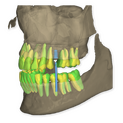

The DSD Interdisciplinary is a digital wax up of the upper and lower arches, designed considering a facially-driven, clinical and functional analysis of the patient.

It is our most comprehensive planning option, and includes all the 3D treatment simulations needed for each case, such as ortho, perio, implants, grafts and orthognathic surgery.

Our 3D simulations showcase facilitate a deeper understanding of the required procedures. This leads to the creation of a broader treatment plan and enables a more efficient communication with your patients.